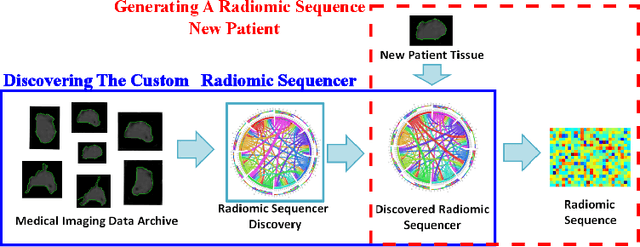

Discovery Radiomics via StochasticNet Sequencers for Cancer Detection

Nov 11, 2015

Radiomics has proven to be a powerful prognostic tool for cancer detection, and has previously been applied in lung, breast, prostate, and head-and-neck cancer studies with great success. However, these radiomics-driven methods rely on pre-defined, hand-crafted radiomic feature sets that can limit their ability to characterize unique cancer traits. In this study, we introduce a novel discovery radiomics framework where we directly discover custom radiomic features from the wealth of available medical imaging data. In particular, we leverage novel StochasticNet radiomic sequencers for extracting custom radiomic features tailored for characterizing unique cancer tissue phenotype. Using StochasticNet radiomic sequencers discovered using a wealth of lung CT data, we perform binary classification on 42,340 lung lesions obtained from the CT scans of 93 patients in the LIDC-IDRI dataset. Preliminary results show significant improvement over previous state-of-the-art methods, indicating the potential of the proposed discovery radiomics framework for improving cancer screening and diagnosis.